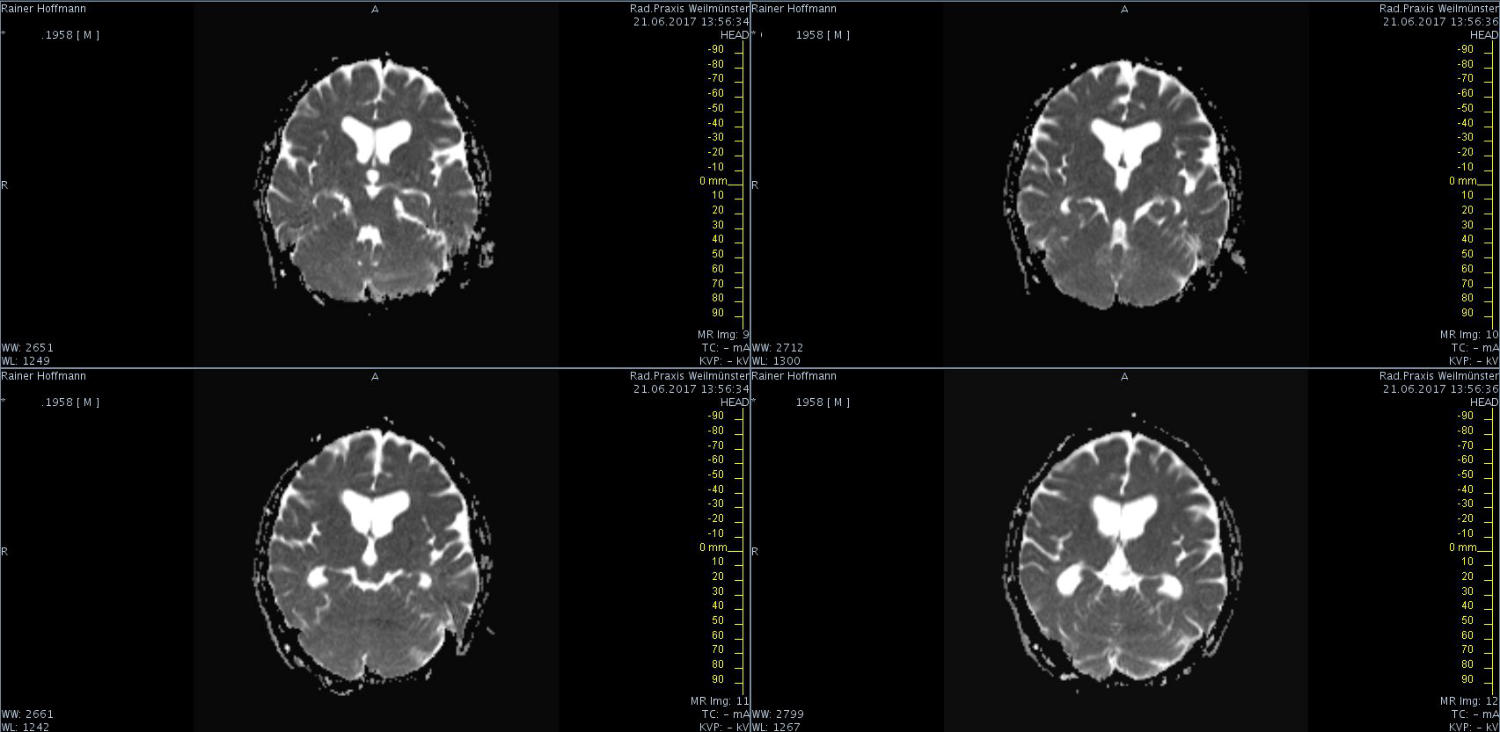

Das ist ja ganz toll, dass Ihr die Seite so schnell gefunden habt. Ich zeige euch jetzt ein ganz, ganz anderes Paßfoto von mir. Es könnte Ähnlichkeiten zu anderen lebenden oder bereits verstorbenen Personen geben. Wenn Ihr das erste Bild oben links anklickt wird es ver- größert dargestellt. Dann kann man mit den Pfeiltasten am unteren Bild- rand durch meinen Kopf blättern. Es gibt nicht viel zu sehen. Vielen Dank an Martina für Ihre Hilfe.

MRT